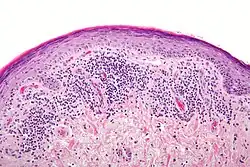

Histopathology

Histopathology of lichen planus

The histologic findings of oral LP can offer strong support for the diagnosis, but are not pathognomonic. Clinical correlation is required. Common histologic findings of oral LP include:[47]

• Parakeratosis and slight acanthosis of the epithelium

• Saw-toothed rete ridges

• Liquefaction (hydropic) degeneration of the basal layer with apoptotic keratinocytes (referred to as Civatte, colloid, hyaline, or cytoid bodies)

• An amorphous band of eosinophilic material at the basement membrane composed of fibrin or fibrinogen.

• A lichenoid (band-like) lymphocytic infiltrate immediately subjacent to the epithelium.

Nonetheless, interpreting the histopathological features of oral LP has been associated historically with high intra-observer and inter-observer variabilities.[66]